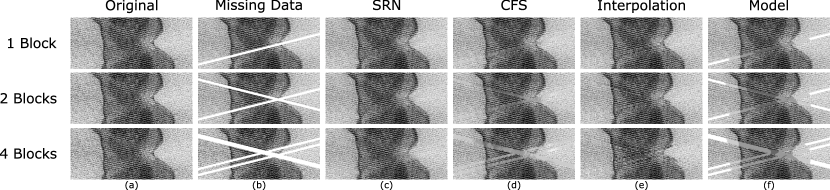

Figure 3 provides a sample of repaired sinogram slices for each method along with the ground truth and the missing data. A visual comparison across all methods of repairing missing sinogram data show the established methods performing in accordance with previously published results, but the Sinogram Repair Network results most closely resemble the ground truth.

Refer to caption

Figure 3: A visual comparison of sinograms for each repair method across the range of missing data shows the sinograms corrected with the proposed neural network most closely resemble the ground truth compared to the other methods.